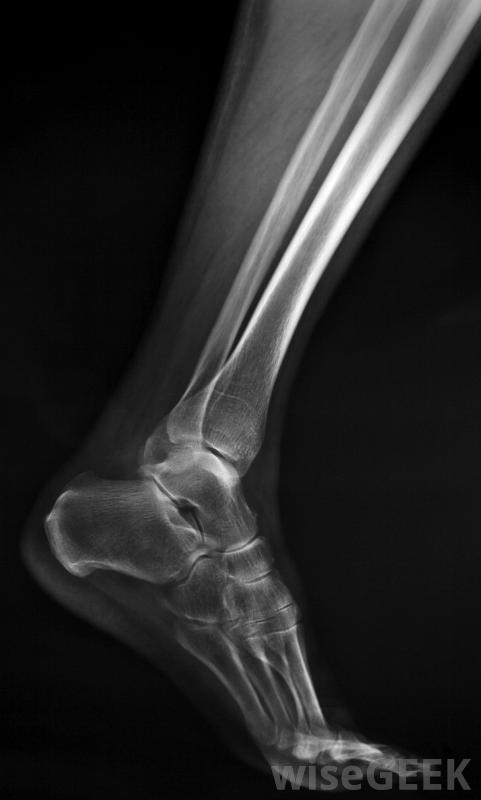

膝盖示意图,显示腓骨。

骨折是腓骨疼痛的常见原因。

腓骨可能因巨大的身体冲击或累积的压力而骨折。承受巨大腓骨疼痛的个体可能患有应力性骨折,尤其是经常参加剧烈的体力活动时。骨折通常发生在膝盖附近,虽然也可能发生中段损伤。虽然大多数骨折可以通过小腿的重新排列和固定来愈合,严重骨折可能需要手术修复。

腓骨骨折是一种常见的疼痛原因,可因身体撞击或累积应力而发生。